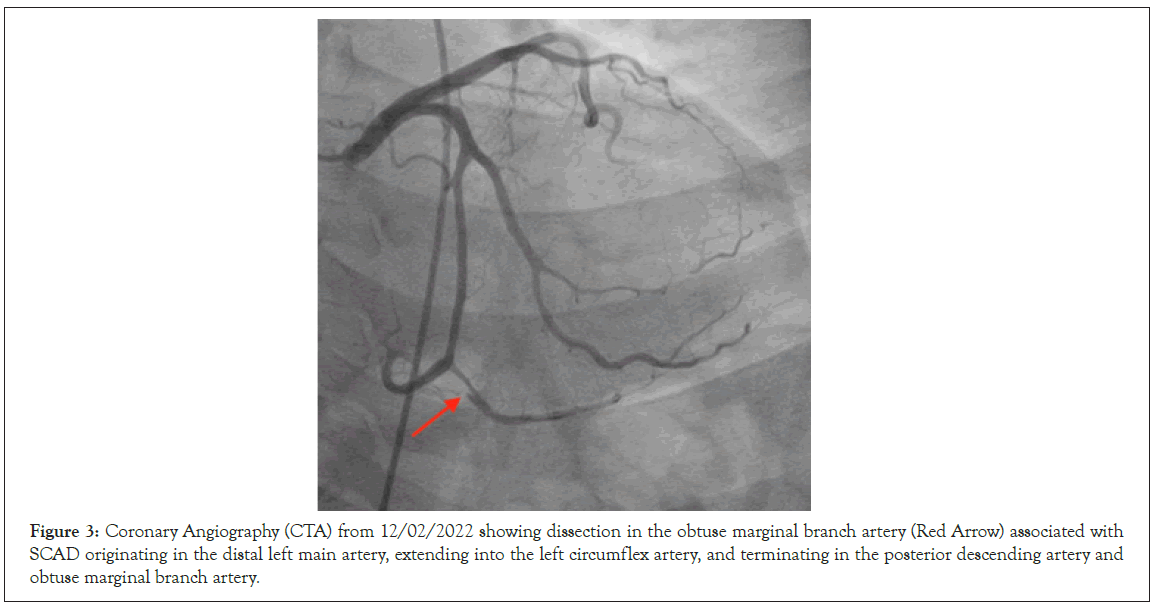

Figure 3: Coronary Angiography (CTA) from 12/02/2022 showing dissection in the obtuse marginal branch artery (Red Arrow) associated with SCAD originating in the distal left main artery, extending into the left circumflex artery, and terminating in the posterior descending artery and obtuse marginal branch artery.

Cardiology discussed with the patient and her family extensively on her condition and initially started her on a nitro drip for aggressive blood pressure control, and then cleared the patient for discharge. Discharge was revoked when her second troponin levels increased, and the recommendation to have her admitted overnight for observation was given. She underwent cardiac catheterization again and was found to have extensive SCAD originating in the distal left main, extending into the left circumflex, and terminating in the posterior descending artery, as well as the obtuse marginal branch. The left circumflex artery remained patient at this time. Dissection appeared slightly worse from previous CTA from 11/26/2022. Etiology was most likely due to uncontrolled hypertension. The patient was then admitted to the ICU for 48 hours with a heparin drip and tight blood pressure control. At that the time of writing, the patient was cleared for discharged by cardiology and was advised to have close follow up via outpatient care (Figures 1-3).